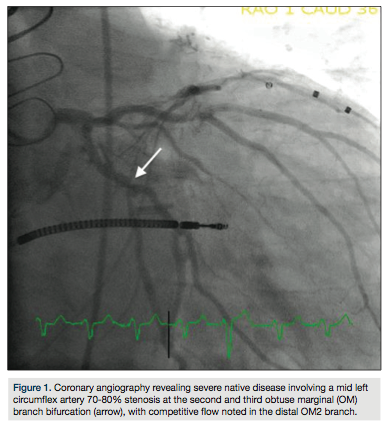

80% stenosis at the second and third obtuse marginal (OM) branch bifurcation, with competitive flow noted in the distal OM2 branch (Figure 1). Selective graft angiography of the left internal mammary artery (LIMA) to the mid left anterior descending artery demonstrated a patent jump graft from LIMA to OM2 with a distal anastamotic 60-70% stenosis (Figure 2). Due to concern for the adequacy of perfusion of the OM2 segment via the native circulation or the jump graft, a strategy to measure the fractional flow reserve (FFR) in the distal OM2 branch was pursued. After maximal hyperemia using intravenous adenosine infusion at 180 mcg/kg/min, maximal FFR was calculated at 0.80 (Figure 3a) with a PressureWire (St. Jude

Medical) in the OM2 segment distal to the graft anastamosis (Figure 3b). A pullback FFR revealed a maximal value at 0.75 (Figure 4a) with the PressureWire wire in the OM2 segment proximal to the graft anastamosis (Figure 4b). Due to the suggestion of borderline perfusion in the distal OM2 segment despite the bypass graft, percutaneous coronary intervention (PCI) of the mid left circumflex artery was performed using a Veriflex 3.0 x 16 mm bare metal stent (Boston Scientific) with excellent angiographic result and brisk retrograde flow through the bypass graft (Figure 5).